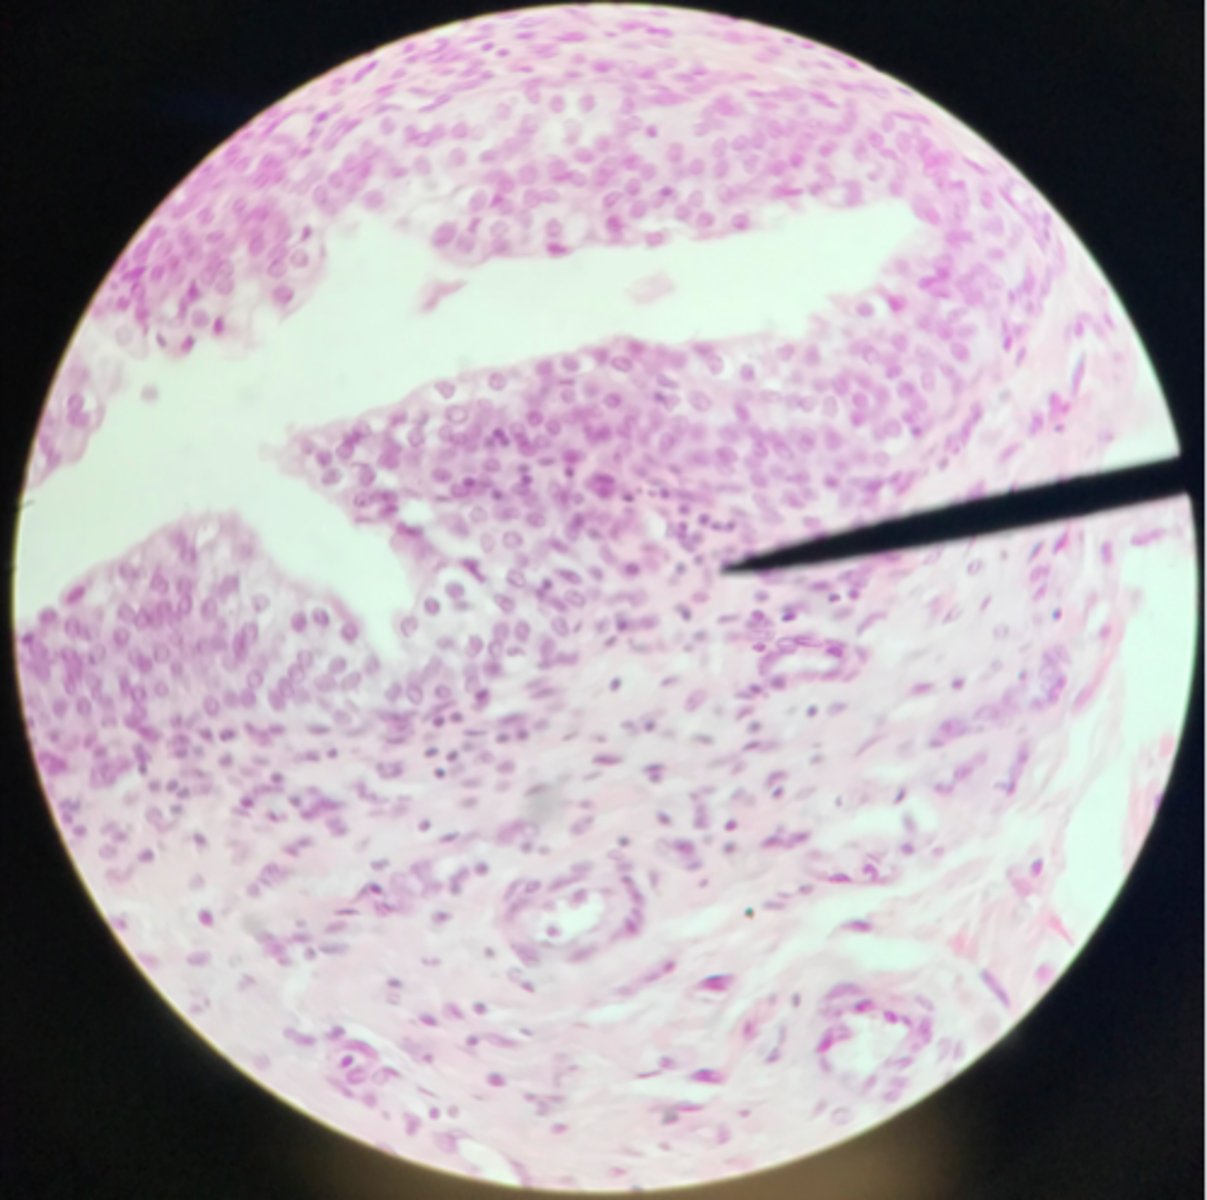

Transitional epithelium of the bladder

What tissue is depicted on the slide above the pointer?

Basement membrane

What cells of transitional epithelium are located where the pointer is at?

Ureter

Transitional epithelium

What structure/organ is depicted on this microscope slide?

What tissue makes up a majority of it?

Transitional epithelium

What type of tissue makes up the inner lining of the ureter?

Urinary bladder

Transitional epithelium

What organ is depicted on the slide? What type of tissue is the main component?

Ureter

Note the smooth muscle layer surrounding the transitional epithelium

What organ is depicted on this slide?